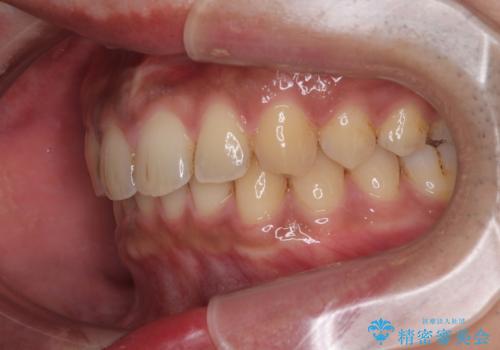

- 上の前歯の正中離開(すきっ歯)と、下顎前歯部の叢生(デコボコ)を主訴に来院された患者様の症例です。

「目立ちにくい装置で治療したい」とのご希望があり、透明のマウスピース矯正であるインビザラインを用いて矯正治療を行いました。